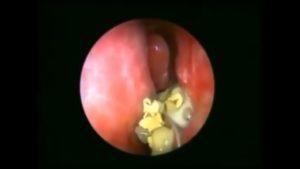

Для выявления грибковой инфекции слизистой носа проводят культуральные исследования соскоба и анализ пораженных тканей под микроскопом.

Выполнение всех указанных процедур возможно только при участии опытного врача-оториноларинголога в клинической или стационарной среде. Этих медицинских исследований, как правило, достаточно для того, чтобы не только выявить грибковую инфекцию в носу, фотографии которой можно найти в сети, но и точно определить ее вид. Это важно для успешного назначения лечения.